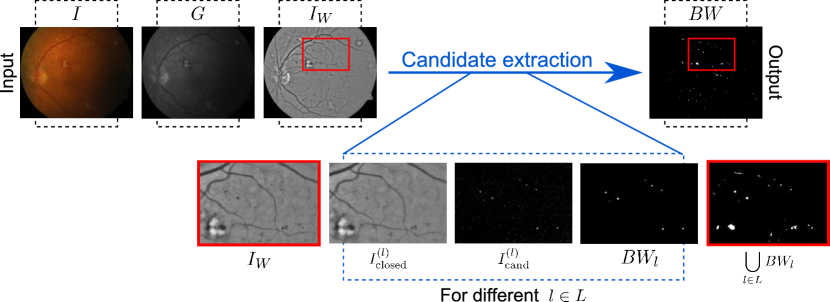

2.1 Candidate detection

Our strategy for candidate detection is illustrated in Figure 3. First, the green band from the original color image is taken, since it is the one that allows a better visual discrimination of the red lesions. To avoid artifacts in the borders of the FOV that might hide potential lesions (Figure 4(b)), a wider aperture of pixels is simulated (Soares et al., 2006) from , where corresponds to the width in pixels of the field of view (FOV). Since our purpose is to develop a system sufficiently general to be applied at different image resolutions, all the relevant parameters are expressed in terms of .

A Gaussian filter with is applied to to reduce noise, resulting in a new image . Afterwards, different morphological closings are performed on using linear structuring elements of length at angles spanning from to with increments of . The set of relevant scales is a fixed parameter that is also automatically adjusted in terms of , as explained in Section 3.2. By taking the minimum response over all the considered angles, an image is obtained in which responses to lesions with sizes smaller than were reduced, and all the remaining structures are still preserved (Walter et al., 2007). A score map is then obtained by:

where CC is a function than counts the number of connected components in the thresholded score map. Once is fixed, a binary map of candidates is obtained by thresholding (Walter et al., 2007). This operation is repeated for different values of to capture potential lesions at different scales, so the binary map of candidates is obtained as . Finally, as might include small candidates which usually are not associated to any pathological region but with noise, all connected structures in with less than pixels are discarded. The automated model selection procedure used to set the values of and and the scales in is described in Section 3.2.